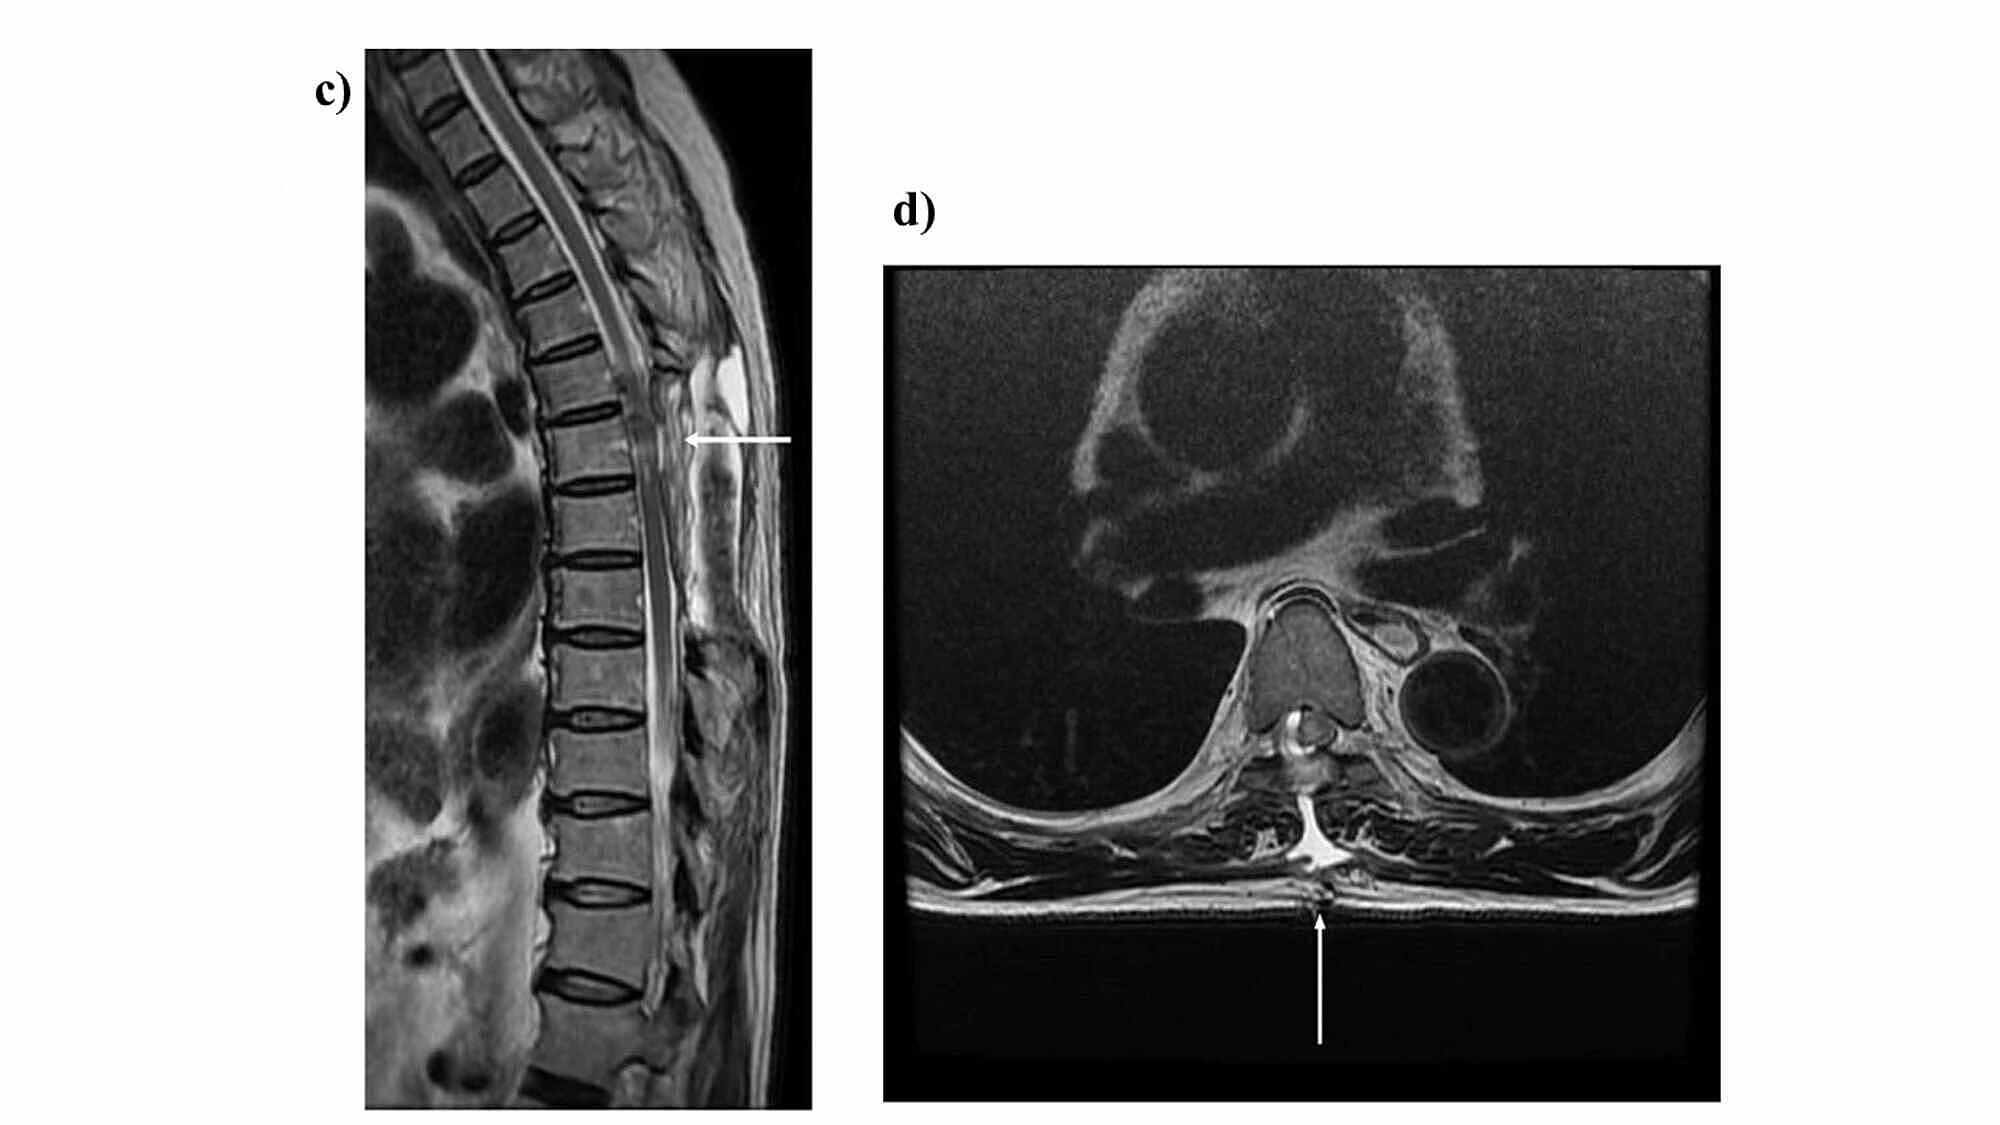

Manual muscle testing showed a decrease in muscle strength in both lower limbs as well as a decrease in deep and superficial sensations in the foot soles to the lower legs. An intradural extramedullary tumor in the Th6 region of the thoracic spine was identified via thoracic spine magnetic resonance imaging; the patient underwent orthopedic surgery, and tumor resection was performed on May 21. Pathological results led to the diagnosis of meningioma, and the patient was transferred to the convalescent rehabilitation ward of our institution on June 8, 18 days after surgery.

Thoracic spinal cord magnetic resonance imaging was performed (Figure 1-2). Based on the aforementioned findings, the following four points were identified as issues: (ⅰ) ataxic gait derived from position sense disturbance due to posterior compression from the tumor, (ⅱ) requirement of a walker due to muscle weakness in both lower limbs, (ⅲ) minimal assistance needed for activities of daily living, and (ⅳ) difficulty returning to work. The following were proposed rehabilitation treatment plans: range of motion training, muscle strength enhancement training, outdoor walking, stair climbing, applied movement training, balance motion acquisition training, activities of daily living, housework, and standing walking under a weight load used to enable a return to work.